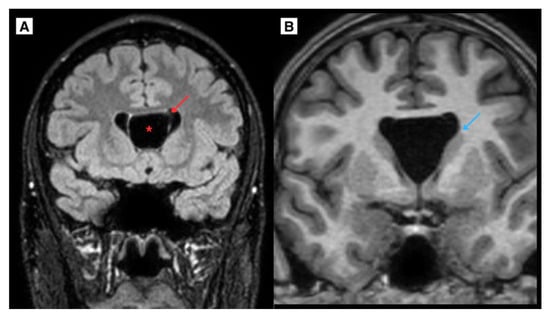

Figure 4.

(A) A CT scan of the brain in the axial plane, performed on an 8 year-old Caucasian male (2011) demonstrated the developmental variant of CSP and CV, with a maximum diameter of approximately 12.2 mm. (B) The same patient’s MRI scan of the brain T2W axial sequence demonstrated a CSP and CV developmental variant. Notably, Blue arrow—linear lesion-like focal changes along the posterior parts of the lateral ventricles, which could be caused by previous mild perinatal injury. Red arrow—septum pellucidum wall, Red asterisk—CSP and CV.